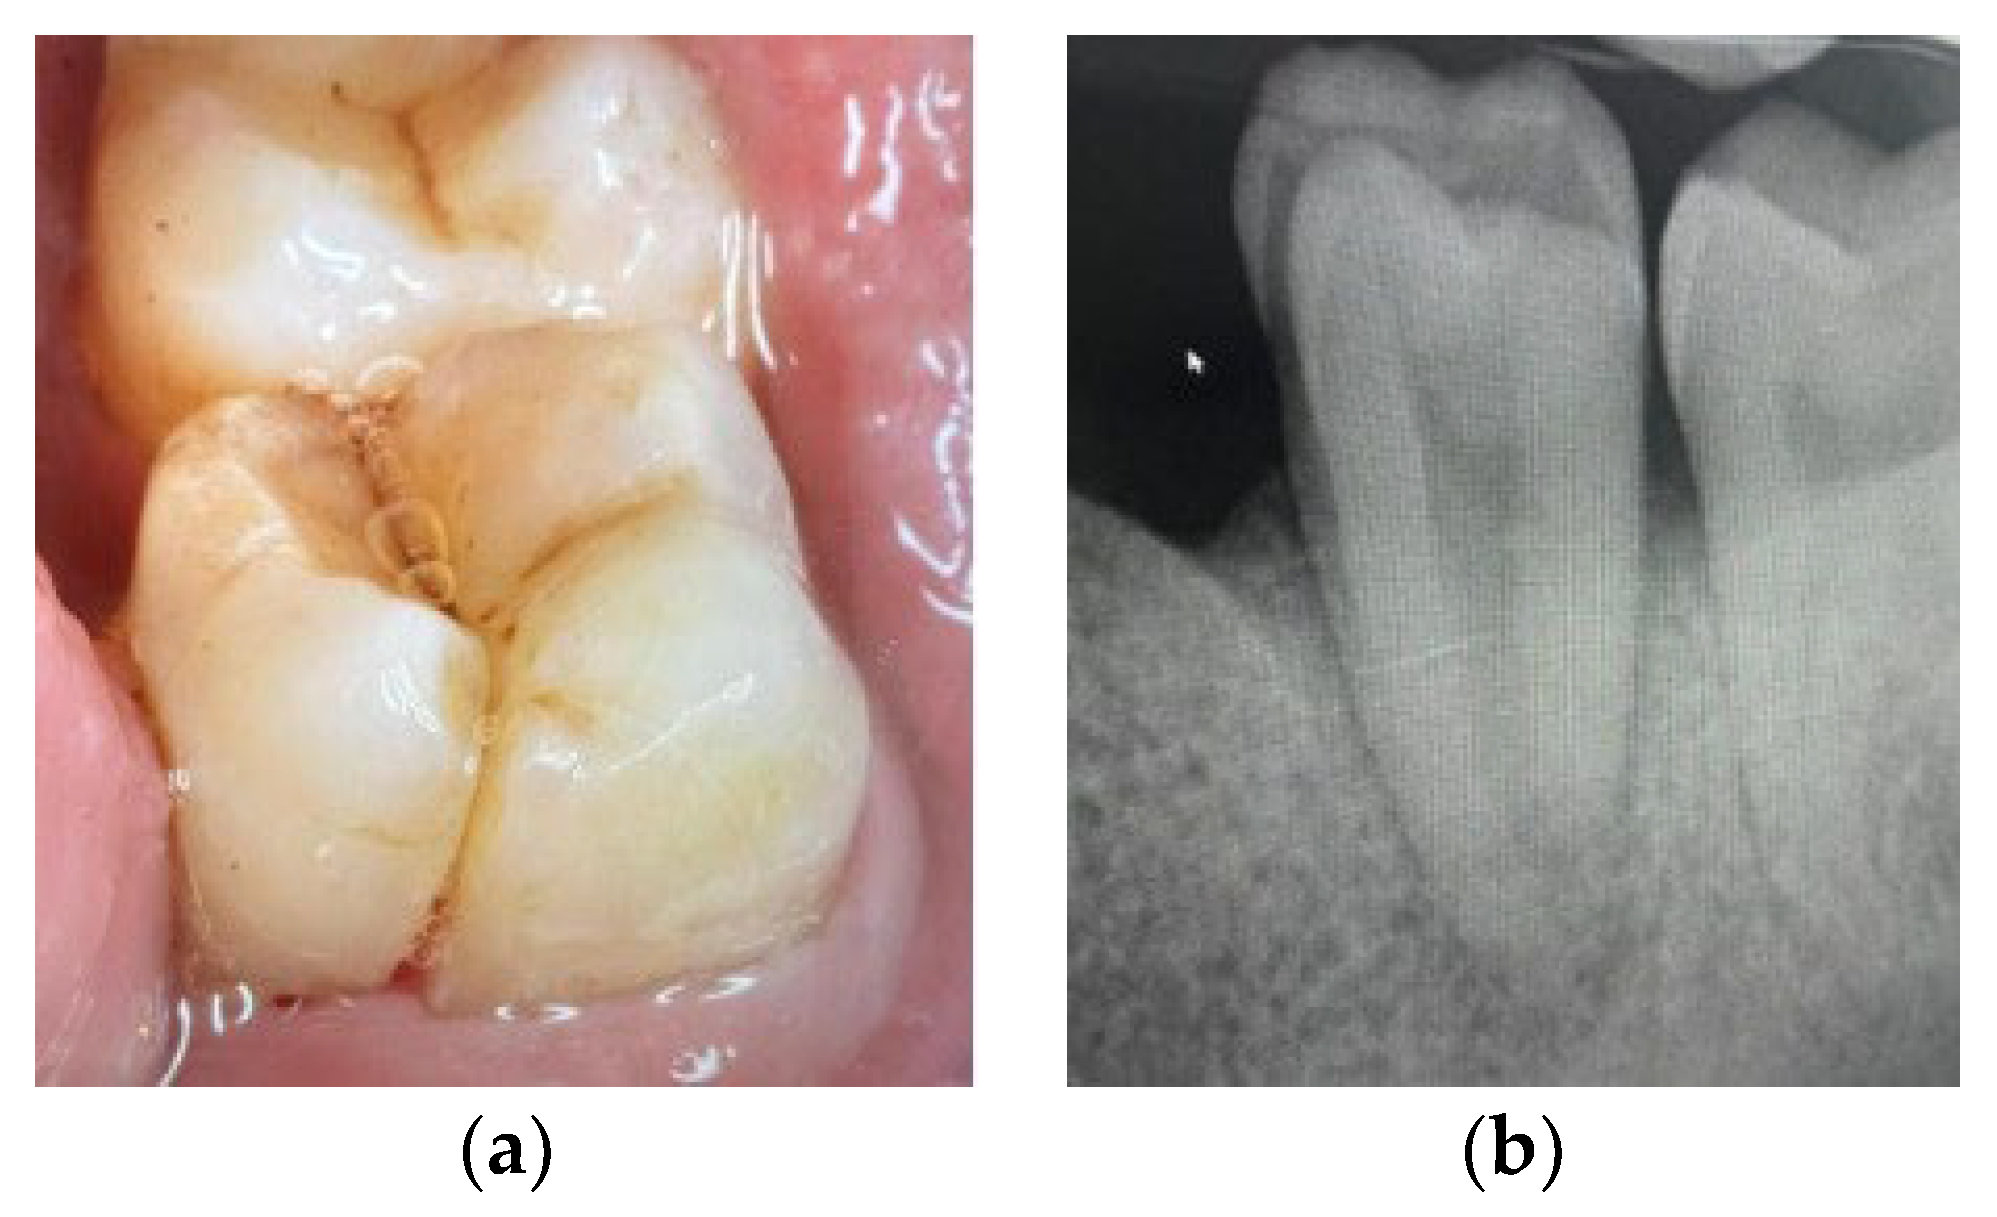

6. Vertical Fractures

- A long history of discomfort related to chronic infection with mild- to moderate-intensity pain, sometimes present during chewing.

- Symptoms persist even following a correctly performed RCT.

- Presence of swelling.

- Sinus tract probing: isolated, narrow and deep periodontal pockets, usually adjacent to the fracture line. Bilateral if the fracture extends on both sides of the root.

- Frequent dislodgment of pins/posts and crowns.

- Separation between the two fragments, with a fracture line along the root.

- Radiographic signs of fragment displacement or longitudinal radiolucencies.

6.1. Treatment Option: Extraction and Implant Placement